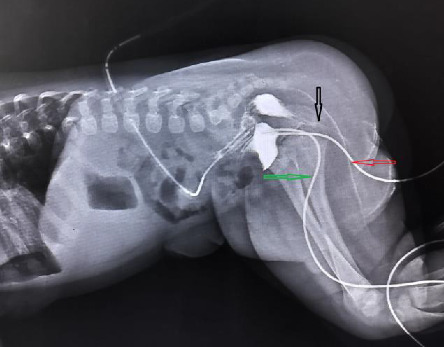

Anorectal malformation (ARM) refers to a group of congenital anomalies that affect the anus, rectum, and sometimes the urinary and reproductive tracts. A full-term male newborn was diagnosed with ARM and rectoperineal (scrotal) fistula during a first clinical screening examination at birth. He also had urethral duplication on the micturating cystourethrogram (MCUG) scan performed on Day 2 of life. The child underwent transverse colostomy at 24 h of life and corrective surgery (posterior sagittal anorectoplasty and urethroplasty) at 6 months of life, followed by colostomy closure after 3 months. This case highlights the importance of the first newborn clinical screening examination to rule out major congenital malformation and the thorough evaluation for associated urogenital defects in the case of ARM before definitive corrective surgeries for better clinical outcomes.